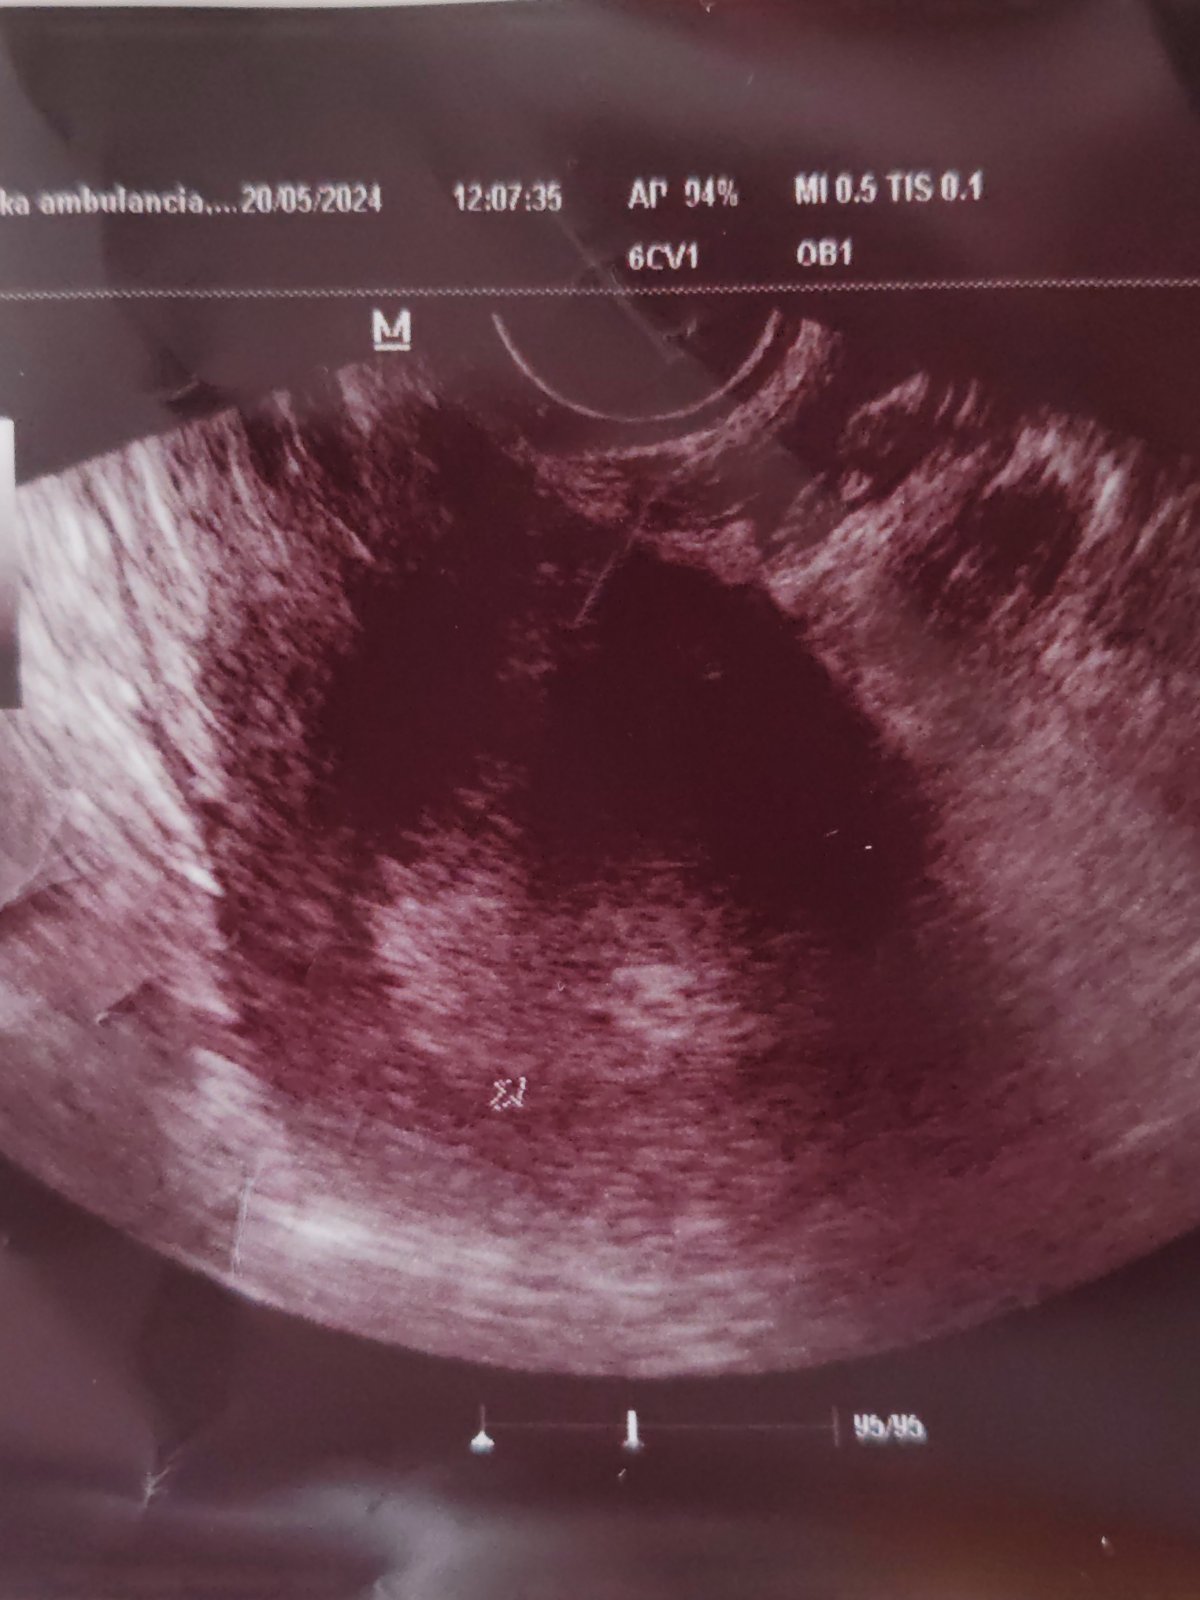

Vidíte na ultrazvuku dva plody?

Dobrý deň tak dneska som bola povedala mi že je to strašne maličké že ak príde menštruácia tak to môže zobrať 😔 ja na tom ultrazvuku skoro nič nevidím. Povedala mi že ona tam vidí len vačok. Dneska podľa menštruácie vychádza že by som mala byť v 6.Týždni. V piatok idem znovu. Vôbec neviem čo si mám o tom myslieť. Je to ťažké pre mňa. Ďakujem Vám všetkým za rady a odpovede.

Ja vidim machule. Ved dr sa asi lepsie vyzna 😉